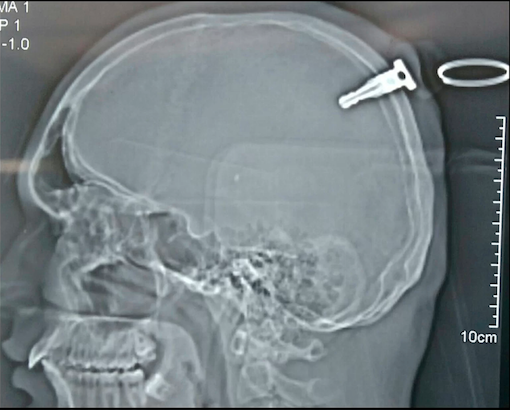

【インド】頭にカギかけた男「バイク用長さ4cm」インドの衝撃X線写真

インド中西部の村で先週、乱闘騒ぎが起こり、19歳の青年が頭にオートバイのカギを突き立てられた。

持ち手にリングをつけたカギの長さは約4センチ。

頭蓋骨を完全に突き抜けて脳に達していたが、奇跡的に一滴の血も出なかった!

正体は持ち手にリングがついた全長3.8センチのバイクのキー。

急きょ、県庁所在地のアフマドナガル市にあるアナンド・リシジ総合病院に搬送され、カギを抜き取るための緊急手術が行われた。

執刀医のシャイレンドラ・ウッタムロ・マーカド(Shailendra Uttamro Markad)医師らのチームは、カギが突き刺さった頭蓋骨の一部をくり抜いて、3時間半かけてカギを取り出した。

「幸運なことにカギは脳のどこも傷つけておらず、内出血はありませんでした。もし血管が損傷して出血が多ければ、脳卒中を起こすか、重い脳障害が残るところでした」

とマーカド医師。

手術は無事成功し、患者は3日後にも退院して村に帰ったというから驚きだ。